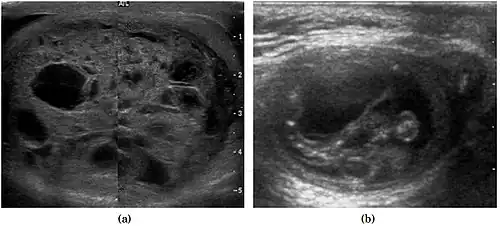

Teratoma Although teratoma is the second most common testicular tumor in children, it affects all age groups. Mature teratoma in children is often benign, but teratoma in adults, regardless of age, should be considered malignant. Teratomas are composed of all three germ cell layers, i.e. endoderm, mesoderm and ectoderm. At ultrasound, teratomas generally form well-circumscribed complex masses. Echogenic foci representing calcification, cartilage, immature bone and fibrosis are commonly seen [Fig. 5]. Cysts are also a common feature and depending on the contents of the cysts i.e. serous, mucoid or keratinous fluid, it may present as anechoic or complex structure [Fig. 6].

Fig. 5. Teratoma. A plaque-like calcification with acoustic shadow is seen in the testis. -

Fig. 6. Mature cystic teratoma. (a) Composite Image. Mature cystic teratoma in a 29-year-old man. Longitudinal sonography image of the right testis shows a multilocular cystic mass. (b) Mature cystic teratoma in a 6-year-old boy. Longitudinal sonography of the right testis shows a cystic mass containing calcification with no obvious acoustic shadow.

Fig. 29. Undescended testis. (a) Normal testis in the scrotum. (b) Atrophic and decreased echogenicity of the contralateral testis of the same patient seen in the inguinal region.